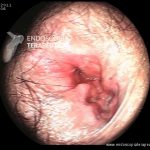

- Doença de Crohn em atividade – proctite

- Doença de Crohn com proctite